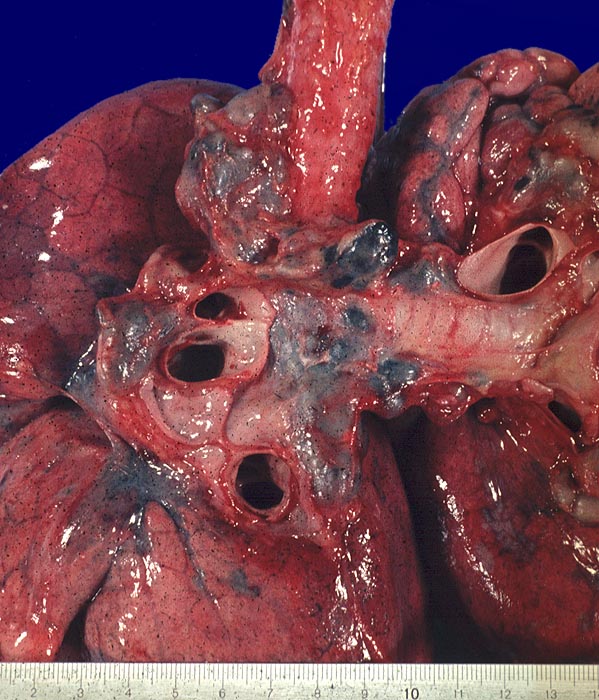

Die Morphologie der Erkrankung ist stadienabhängig. Initial findet sich eine lymphozytenreiche Alveolitis mit wenigen kleinen Granulomen. Die Granulome bestehen aus Aggregaten epitheloider Histiozyten teilweise mit Beteiligung von mehrkernigen Riesenzellen. Im Verlauf entwickeln sich zellreiche Granulome entlang der bronchovaskulären Bündel und der Interalveolarsepten, welche später konfluieren und vernarben. Die Riesenzellen können Asteroidkörperchen (sternförmige Kristalle) oder Schaumannkörperchen (lamelläre Verkalkungen) enthalten. Ein Teil der Patienten entwickelt eine irreversible Lungenfibrose.

• Zahlreiche produktive, nicht nekrotisierende Granulome aus dickleibigen Epitheloidzellen, Riesenzellen vom Langhanstyp und Lymphozyten.

• Ausgeprägte Fibrosierung der Granulome.

• Herdförmige Vernarbung des Lungenparenchyms.

• Bevorzugte Lokalisation der Granulome im Bereich von Bronchiolen und Pulmonalarterienästen. Das sollte der Kliniker dem Pathologen mitteilen: